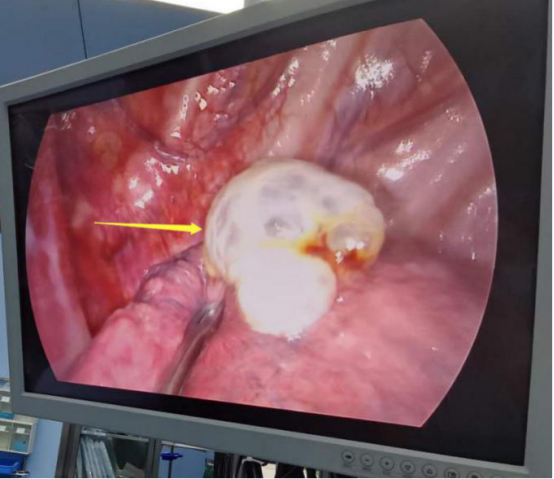

手術過程中。

患者肺大泡明顯,術后切口較小。